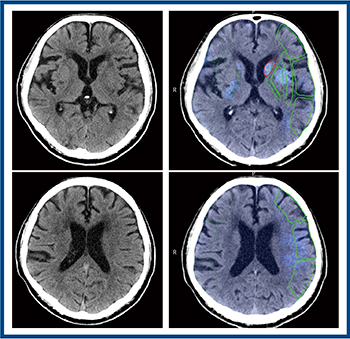

単純CTの解析を行うHemorrhage analysisは,正常画像と比較してCT値および画素値が高い領域(出血領域)を抽出し,強調表示する(図1 a)。また,Ischemia analysisは,正常な脳と比較してコントラストが低下している領域を抽出し,ASPECTS(Alberta Stroke Program Early CT Score)に沿って早期虚血性変化を強調表示する(図1 b)。

図1 Abierto RSS for Neuroの単純CT解析のアプリケーション

頭部単純CTでは出血を認めず,Abierto RSSでは脳の左半球の早期虚血性変化が表示された(図3)。急性期脳梗塞疑いにてperfusion CTを施行し,Abierto RSSにて自動解析が行われた。結果画像は自動でPACSに転送されるため,操作室で診療放射線技師が,各種マップ画像や4D画像にて閉塞血管などを一元的に確認すると同時に,救急外来では主治医が適応判断を行い,カテーテル室では治療の準備を進めることができる。図4はAbierto RSSの解析結果であるが,虚血コア体積は68.7mLとやや大きいものの,ペナンブラ領域も広汎に認め,また,mismatch ratioは3.1であり,血栓回収療法の適応と判断した。

図3 頭部単純CTにおける早期虚血性変化の表示